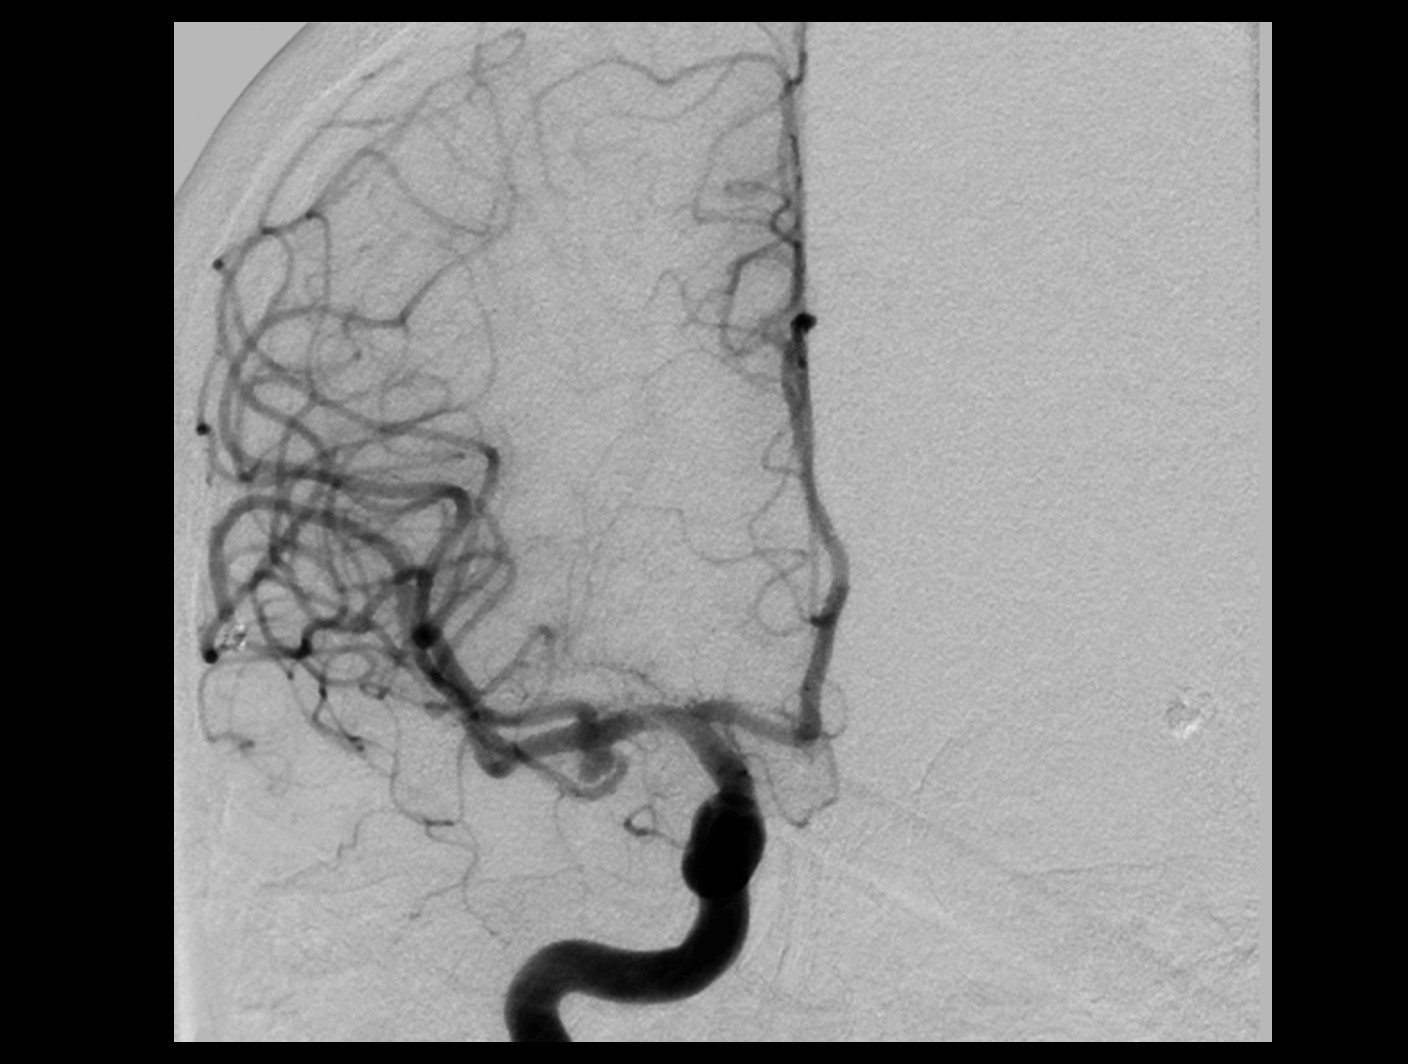

Aneurisma incidental relacionado a artéria cerebral média diagnosticado após investigação de cefaleia. Realizado tentativa de embolização com micromolas sem sucesso, sendo optado pelo tratamendo endovascular com stent redirecionador de fluxo Fred Jr 03 x 14 x 19 mm.